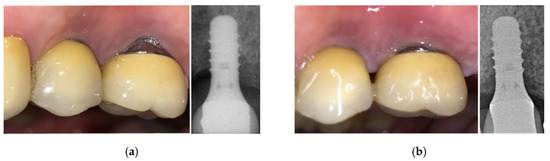

The first reported clinical case is a 48-year-old man reporting swelling and pain 15 days after the implant positioning (before the loading phase). A follow-up X-ray was used to plan the treatment with the newly developed device. After four therapeutic sessions (one week apart from each other, up to 90% of the maximum power), the symptoms disappeared and the implant was fully recovered, as also visible from the follow-up X-ray (Figure 13). Two months later, after a further follow-up X-ray, the prosthetic finalization was made (loading phase).

The second clinical case is a 69-year-old man with pain and bleeding on probing. Following a session of oral hygiene, the patient was treated with the new developed device. After four therapeutic sessions (two per week, each consisting of seven consecutive therapeutic signal deliveries, up to 90% of the maximum power), the implant could be considered recovered and pain disappeared after the first therapeutic session (Figure 14). Monthly check-ups were planned and follow-up X-rays confirmed the positive outcome of the therapy.

Figure 13. Clinical case No. 1: dental implant (a) before and (b) after the treatment.

Bioengineering 07 00087 g013

Figure 14. Clinical case No. 2: dental implant (a) before and (b) after the treatment.

Bioengineering 07 00087 g014